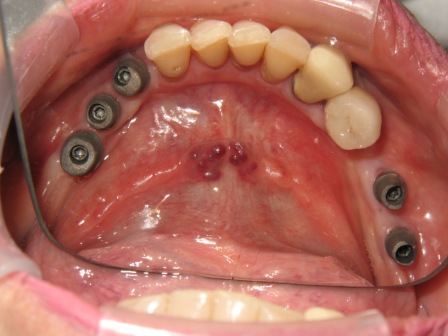

sage-dental-before-1